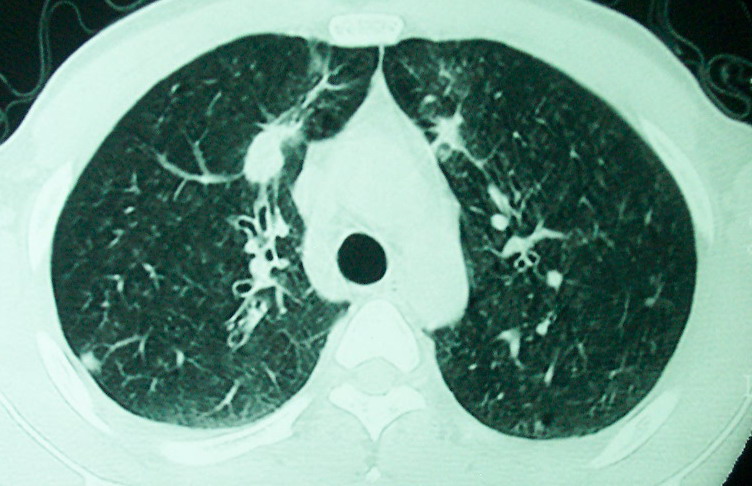

m      37y      发热   咳脓痰月余      ct肺脓肿但住院抗炎治疗后双肺内结节不知该如何解释

治疗后见左肺下野病灶较前缩小但双肺内结节影似无变化请较各位老师该如何下结论    治疗前wbc14.5 治疗后wbc 11.0

血源性肺脓肿,一般由原发感染灶引起脓毒败血症,在肺部形成小脓肿,病变变化快,容易形成肺气囊,脓气胸,主要与转移瘤鉴别,通过临床病史可分

空洞内可见小结节样密度影考虑合并真菌感染

我看是不是可以两元化来解释,左肺下叶还是肺脓疡,而其余病灶考虑肺癌伴肺内转移,我看右肺上叶尖段病灶可见明显毛刺改变为原发病灶.

如果你仔细的同层面对比,你会发现所有的病灶均有比较明显的吸收、缩小。病变的形态,特别是脓肿的形态、壁的厚薄、内壁均有很大的变化,均在往好的方面发展。与临床症状、血像均符合,治疗效果比较显著,就是肺脓肿并双肺的化脓性炎症灶。